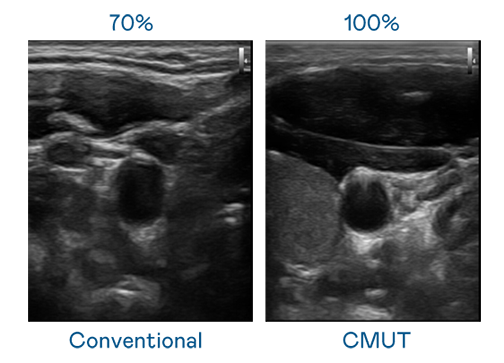

CMUT 技术是一种用电容式微机电元件来产生超音波讯号的技术。与传统 PZT 压电式技术相比,CMUT 频宽增加 30%,更宽频的超音波讯号让影像解析度大幅提升,是实现高影像品质医疗超音波扫描、促进精准医疗发展的关键技术。

大频宽带来超清晰影像

超音波影像的解析度高低,首先取决于探头能发出的讯号频宽。聊斋花红弄月高清版完整在线观看 CMUT 可提供高清晰的超音波讯号,提供高频宽、高灵敏度、影像纹理细节更高的超音波影像,协助医护人员缩短影像判读时间及利用精准的医疗影像进行诊断。